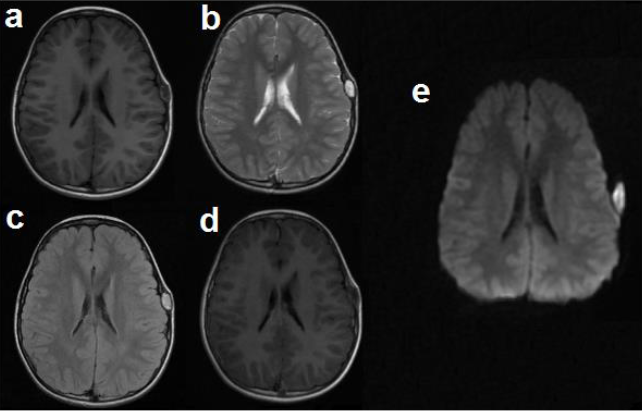

En estudio de Tomografía Computarizada simple de cráneo realizada un mes previo al acto quirúrgico valorada en cortes axiales y coronales se observa en ventana ósea lesión ocupante de espacio (LOE), hipodensa, extradural de forma ovoidea, de característica lítica, ubicada en región parietal izquierda con aproximadamente 8,8x17 mm de diámetro. Ventana parenquimatosa sin alteraciones (Fig. 1a, 1b). En resonancia magnética cerebral contrastada se observa imagen extradural, de forma ovoidea, bien delimitada con bordes regulares de características quísticas en región parietal izquierda, de comportamiento heterogéneo, hipo e isointensa en secuencia T1, hiperintensa en T2 y FLAIR, sin captación tras la administración de contraste endovenoso y restricción en Difusión (Fig. 2). Se realizó reconstrucción 3D postquirúrgica donde se observa defecto óseo en hueso parietal izquierdo (Fig. 3).

La resonancia magnética es el estudio de elección para el diagnóstico de los quistes epidermoides. Se evidencian como lesiones hipointensas en T1 e hiperintensas en T2 y FLAIR.También es de gran utilidad la difusión por resonancia magnética para el diagnóstico diferencial ya que éstas lesiones muestran una señal intensa en esta secuencia (8). Los quistes epidermoides no muestran realce posterior a la administración de contraste endovenoso, siendo esto una característica útil para el diagnóstico de los mismos (18). Se ha reportado en la literatura que el tratamiento definitivo de los quistes epidermoides es la resección completa de la lesión para así evitar la recurrencia y el riesgo de meningitis aséptica, por otro lado, Kakane V et al. reportan que puede considerarse una resección conservadora de la lesión si esta se encuentra en proximidad a estructuras neurovasculares o parénquima cerebral vital, dado que los quistes epidermoides presentan un crecimiento lento (19). El pronóstico a largo plazo es excelente si se realiza la resección total de la lesión y su cápsula (20). En nuestro caso se logró la resección total de la lesión sin complicaciones postquirúrgicas. Algunos autores sugieren el lavado del campo quirúrgico con dexametasona disuelta en solución fisiológica para evitar complicaciones como la meningitis química para la cual se describe una incidencia en quistes epidermoides intradurales de hasta 40% (21).